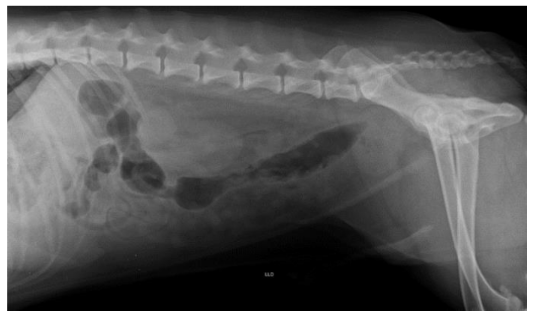

Ao exame radiográfico não foram observadas litíases radiopacas em vesícula urinária ou trajeto uretral, apenas discreta quantidade de conteúdo gasoso, provavelmente proveniente do procedimento de sondagem uretral.

Diante dos resultados encontrados nos exames supracitados foi indicada a realização de cistotomia para retirada dos cálculos.

Durante o procedimento cirúrgico, a equipe relata que ao abrir a vesícula urinária esta encontrava-se com paredes bastante espessas, presença de pus em região interna e pontos tendendo à início de necrose. Porém, não foram encontrados todos os cálculos anteriormente visualizados em exames de imagem, apenas um deles, que foi retirado.